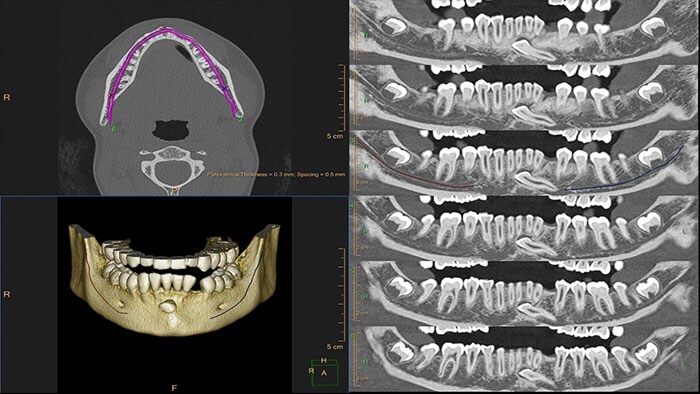

Planning for oral surgery

In maxillofacial trauma cases, the course of treatment can often only be decided after a surgical consult. CT Dental Planning is designed to support enhanced surgical planning, and facilitate collaboration between radiologists and surgeons.